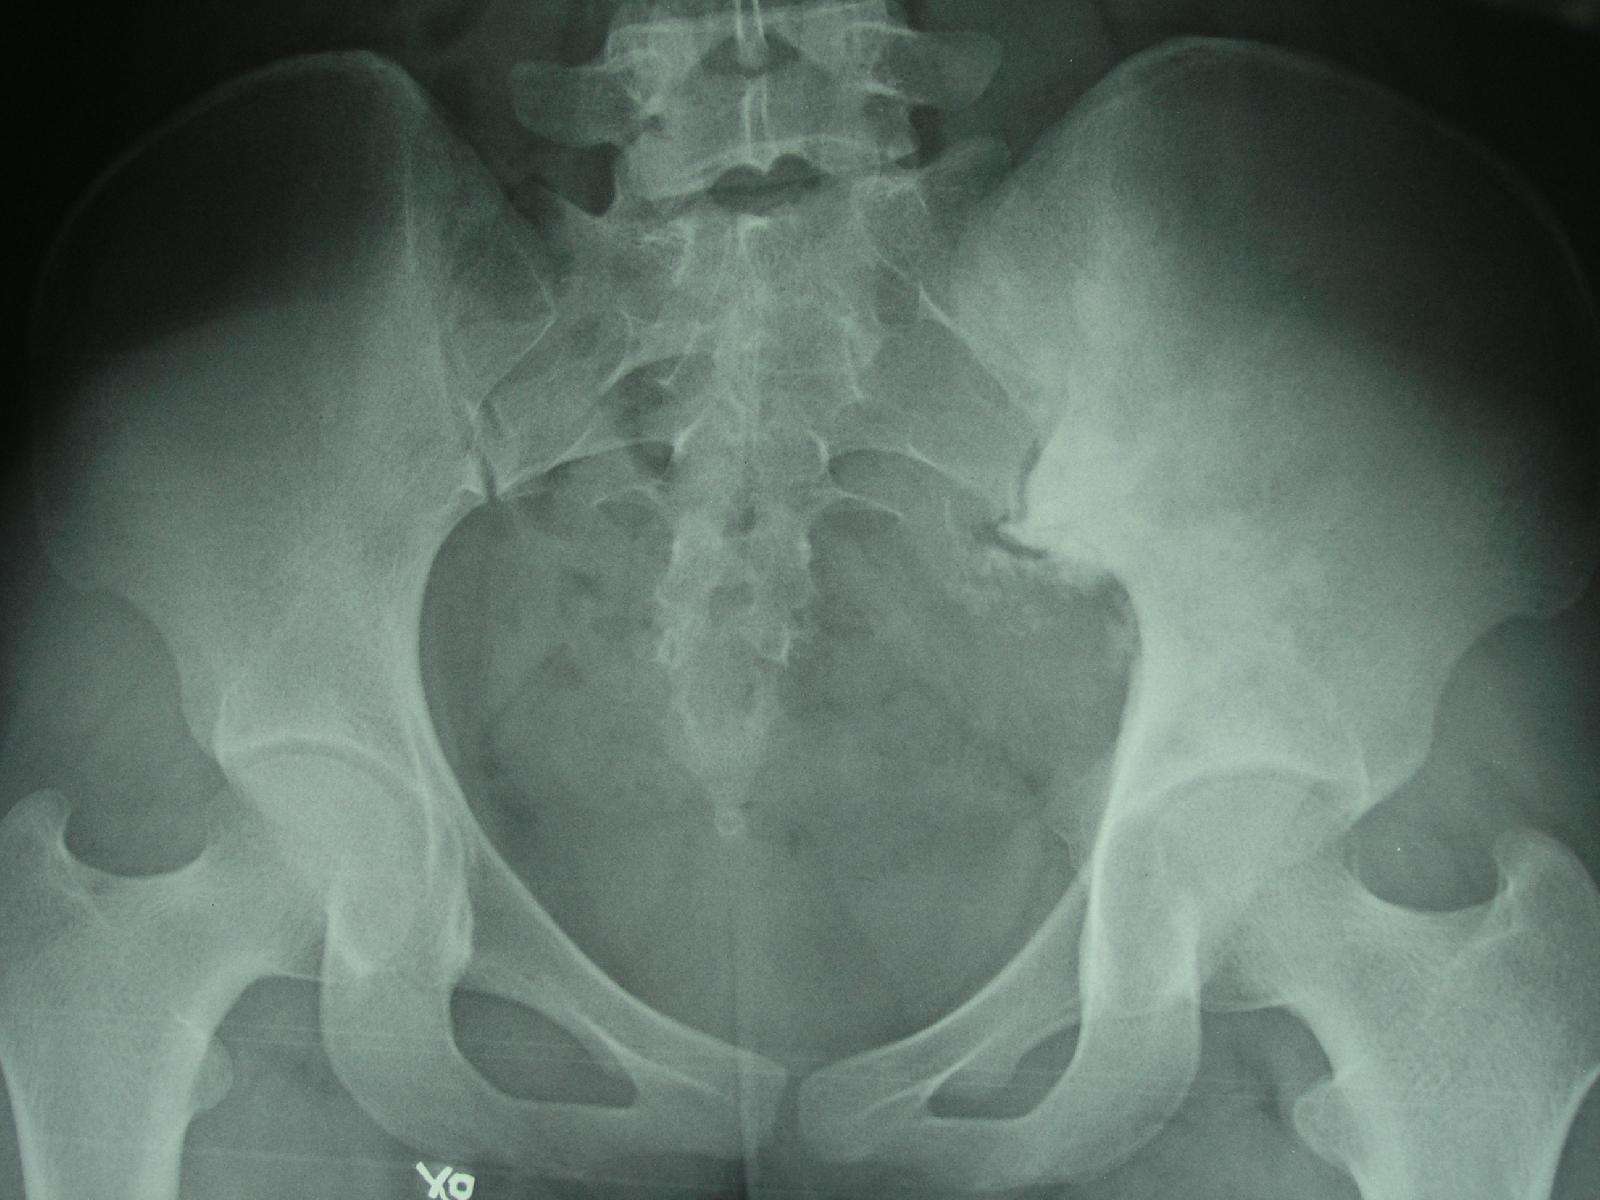

2. 病例2:女 25岁,左股骨下段骨肉瘤并病理性骨折,术前大剂量化疗后行瘤段广泛切除定制人工关节置换术。

术前X线片